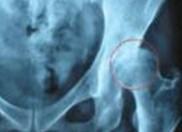

骨骼内气泡的特殊作用,骨骼是一个不能扩张的组织。股骨、肱骨、胫骨等长骨内黄骨髓含脂量高,血流很缓慢,减压时会产生多量气泡,直接压迫骨骼内的血管;骨骼营养血管内也有气栓与血栓,容易造成局部梗塞,最终缓慢地引起无菌性的缺血性骨坏死。又称减压性骨坏死(dysbaric osteonecrosis)或无菌性骨坏死,其形成除了骨骼内气泡的特殊作用外,还有脂肪栓塞、血小板凝聚、气体引起渗透压改变、自体免疫等作用的综合结果。